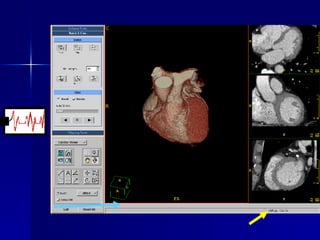

Target Applications Coronary Arteries Stenosis Evaluation Coronary Bypass Graft Patency Volume rendering and Virtual Endoscopy of: Coronary Arteries Pulmonary arteries Bronchi Cardiac Motion analysis Cardiac Functional Analysis Cardiac Perfusion

Functional –  Ejection Fraction Diastole Volume = 163 cc Systole Volume = 77 cc Ejection Fraction   = 53%